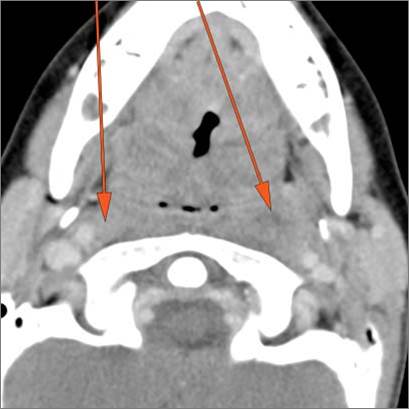

There is reactive cervical lymphadenopathy. [Yes/No]

There is suppurative cervical lymphadenopathy. [Yes/No]

If there is suppurative cervical adenopathy the purulent material outside the lymph node(s) capsule(s). [Yes/No]